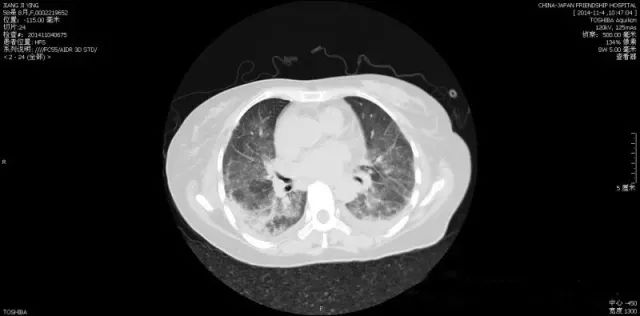

六、胸部CT:

部分多发性肌炎患者可以累及到肺脏,出现间质性肺炎表现,故需要性胸部CT评估肺部病变情况。